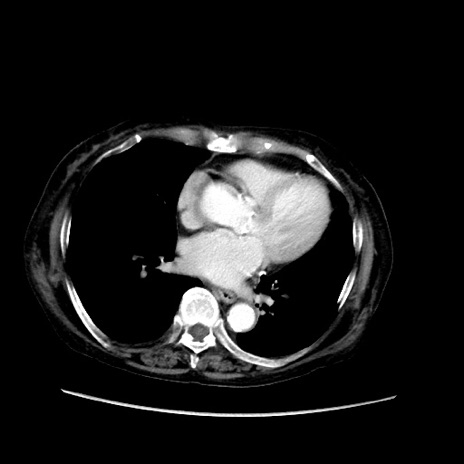

症例31(横断像)

【症例】80歳代 女性

【主訴】腹部膨満感

【現病歴】他院にて肝硬変にてフォロー中。1週間前から便秘、腹部膨満感、臍部腫瘤あり受診となる。

【既往歴】肝硬変

【身体所見】腹部膨隆あり、皮膚変化なし、疼痛なし。

【データ】WBC 4600、CRP 0.25